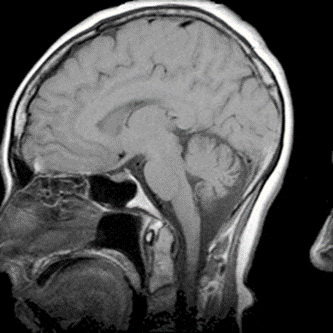

Który artefakt uwidoczniono na skanie RM głowy?

A. Efekt uśrednienia.

B. Poruszenie pacjenta.

C. Zawijanie obrazu.

D. Przesunięcie chemiczne.